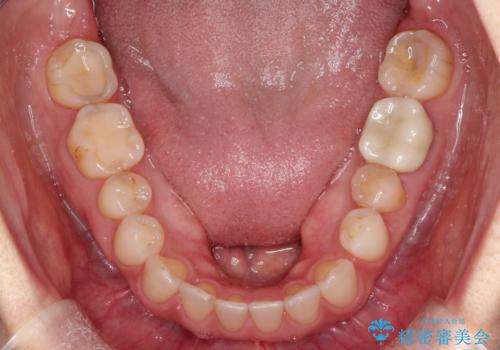

- 過去に矯正を行ったあと、前歯の後戻りを主訴に来院されました。

マウスピース矯正にて隙間を閉じる計画をたて、治療を行いました。